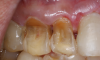

Fig 2. Facial erosion of maxillary (Fig 2) and mandibular (Fig 3) anterior teeth.

Figure 2

Another intrinsic factor is the patient's gastric acid entering the oral cavity. The source of intrinsic stomach acid may range from rumination or gastroesophageal reflux to chronic alcoholism, pregnancy, or vomiting caused by anorexia nervosa or bulimia nervosa.13 Figure 1 through Figure 3 show the radiographic presentation and clinical examples of dental erosion in advanced stages in the same patient caused by the combination of bulimia nervosa and chronic alcoholism.